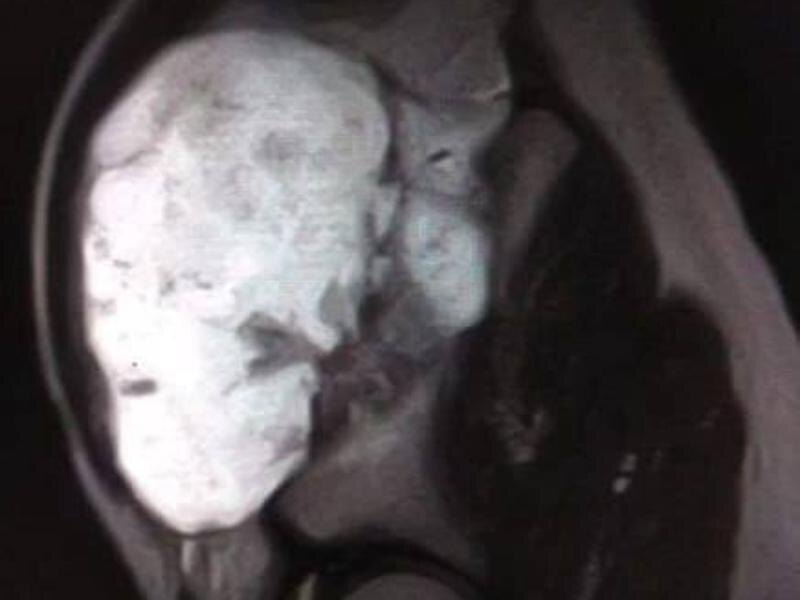

Юный пациент обратился к медикам с жалобами на дискомфорт и ограничение подвижности. При обследовании специалисты обнаружили внушительный нарост на кости размером 12×9×7 сантиметров. По словам врачей, образование не только мешало нормально двигаться, но и представляло серьёзную угрозу – при дальнейшем росте оно могло повредить тазобедренный сустав и привести к осложнениям.

Медики приняли решение о проведении операции. Хирургическое вмешательство оказалось непростым из-за размеров образования и его расположения, однако врачам удалось аккуратно удалить нарост и избежать повреждения важных структур.